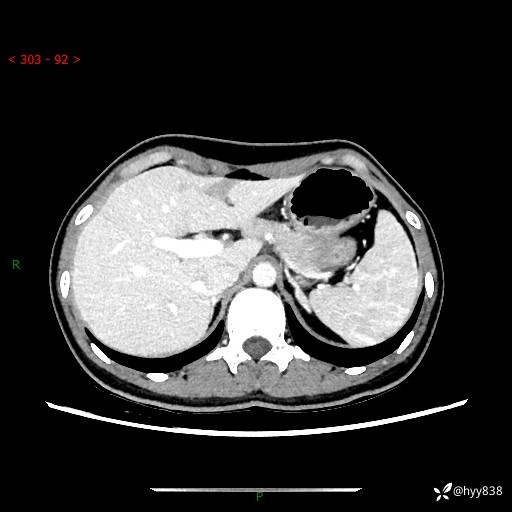

性别:女

年龄:23岁

简要病史:外院发现肝结节,来我院进一步增强确诊

上腹部CT平扫+增强